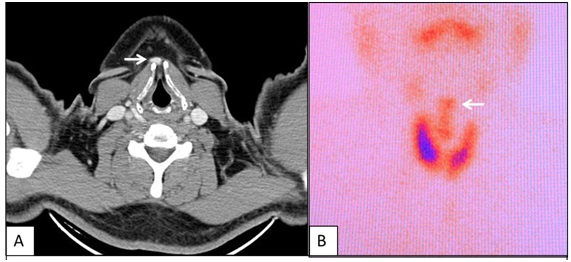

Caso 3: Paciente varón de 47 años, a quien incidentalmente se le encuentra en una tomografía cervical presencia de tejido captador de contraste sobre la línea media, con intensidad similar al tejido tiroideo (fig. 4A). Se le realiza una gammagrafía para detección de posible tejido tiroideo ectópico, que confirma el hallazgo (fig. 4B).